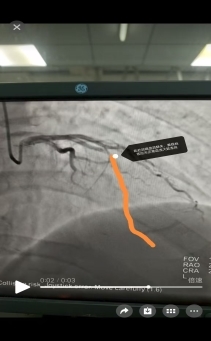

37岁的曹先生上午在家中突发剧烈胸痛、大汗淋漓,被紧急送往我院。入院后,急诊科迅速为他进行了全面检查,但心电图和早期心肌损伤标记物均为阴性,遂收入住院进一步诊治,我院心内二科黄涛医生凭借丰富的临床经验,敏锐地察觉到患者病情的严重性,果断判断这是一例不典型早期心梗。病情就是命令,时间就是生命!心内二科胸痛中心团队迅速启动绿色通道,一键激活导管室,各参与救治人员间紧密配合。在患者进入导管室后,团队凭借精湛技术,快速完成冠状动脉造影,明确患者前降支近段完全闭塞,立即实施冠脉介入治疗开通罪犯血管,仅用数分钟就恢复了前降支远段血供,为患者赢得了宝贵时间。术中血管开通后,曹先生胸痛症状随即缓解。